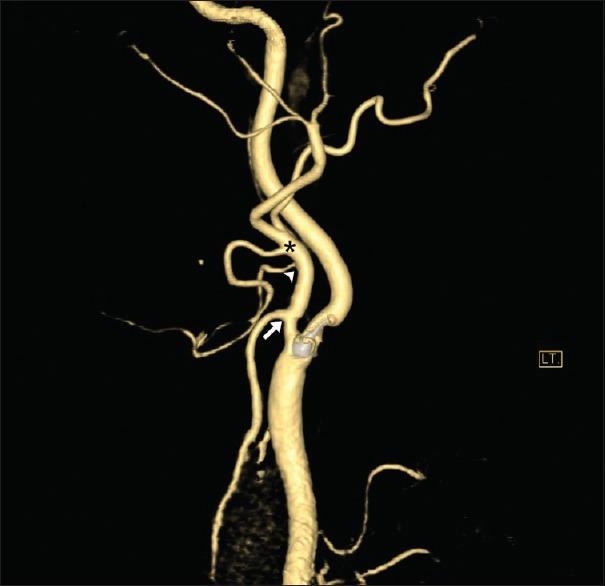

We studied levels of carotid bifurcation compared relatively with the level of the vertebral body and ipsilateral angle of the mandible and its branching pattern using computed tomographic angiogram (CTA) carotid with multiplanar reconstruction and three-dimensional imaging in 100 CTA studies.

我们在100例计算机断层血管造影(CTA)研究中,使用多平面重建和三维成像的CTA颈动脉,将颈动脉分叉的位置与椎体水平和同侧下颌角进行相对比较,并研究其分支模式。

大多数颈动脉分叉位于C3 - C4椎体水平,12%被认为是高位分叉。83.5%的颈动脉分叉位于下颌角以下。67.7%的样本中,甲状腺上动脉、面动脉和舌动脉分别起自颈外动脉的不同分支。29.2%的样本中,面动脉与舌动脉共干发出,比以往尸体研究更为常见。2%的样本中,舌动脉与甲状腺上动脉共干发出,而枕动脉的分支模式变异较大。

结论

CTA是对接受颈动脉内膜切除术及其他颈动脉手术患者进行颈动脉系统术前评估的有效且可靠的方法。我们的研究中发现高位颈动脉分叉的比例较高,与其他亚洲尸体研究结果一致。我们推测亚洲人的颈动脉分叉位置往往比白种人略高。